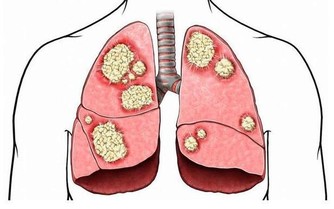

此外,大腸中腐敗食物和細菌產生的毒素,如果不能及時排出,被機體吸收後可使內臟功能而發生障礙,增加自身“中毒”的機會,便秘、便血、腹瀉、腸易激、排便惡臭、放臭屁、口臭、膚色粗糙晦暗、直腸癌急其他消化系統疾病隨之而來。